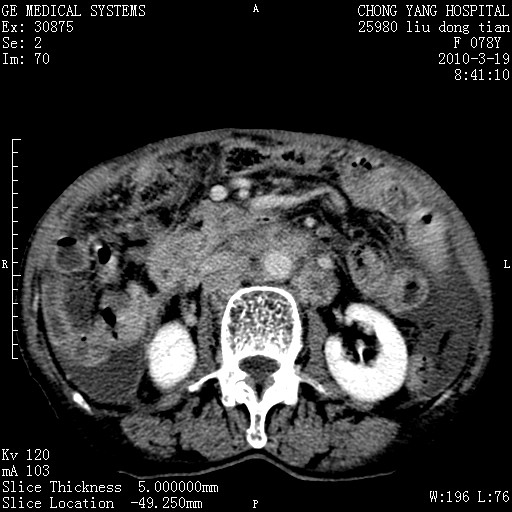

标题: CT25199:F 78Y 腹胀半年 消瘦乏力 [打印本页]

胆囊壁增厚并明显强化,胆囊癌伴多发转移瘤可能性大,淋巴瘤不除外,右肾囊肿,胸腹水.

考虑nhl,肝、脾、腹膜腔及腹膜后多发淋巴结受侵,腹水,右肾囊肿,慢性胆囊炎,右侧少量胸腔积液。

首先考虑恶性淋巴瘤 。

胰头有肿块形成,胰头ca伴肝脾、腹膜腹膜后转移

胆囊有软组织影有强化,支持胆囊癌,肝脾、腹膜后淋巴结转移。

nhl的淋巴结多围绕主动脉,而且主动脉会移位,所以不考虑nhl。

分开来讲:肝左叶、尾叶病灶有不均强化像肝癌;

脾脏病灶无强化,像多发囊肿或淋巴管瘤,不除外淋巴瘤(低强化);

胆囊增生性病变:胆囊癌,腺肌增生症,慢性胆囊炎;

肝门、胰腺头、腹膜后多个团块: 淋巴瘤,转移;

腔静脉肝内段细小有无布加可能?

一元论最好了 淋巴瘤所致改变; 胆囊癌转移不像,胆囊周围肝组织清晰,肝癌淋巴结转移?三元论都不止。

胰头ca伴肝脾、腹膜腹膜后转移!

最后报的胰头癌多发转移,脾脏单独考虑囊肿或淋巴管瘤。